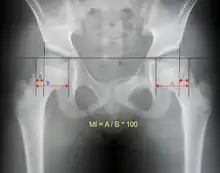

An anterior-posterior (AP) X-ray of the pelvis and a cross-table lateral X-ray[24] of the effected hip are ordered for diagnosis.[4][5][16] The size of the head of the femur is then compared across both sides of the pelvis. The affected femoral head will appear larger if the dislocation is anterior, and smaller if posterior.[7] A CT scan may also be ordered to clarify the fracture pattern.[20]